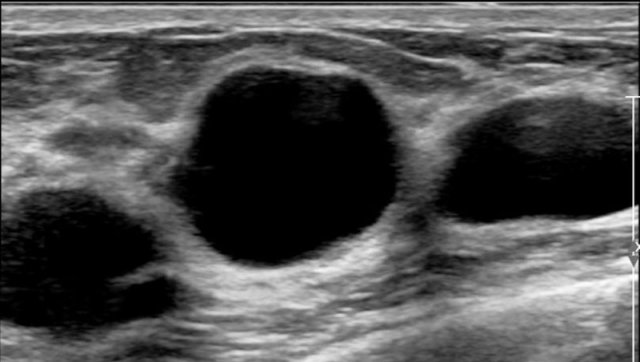

Here a typical example of multiple cysts in a woman who felt a lump in her breast.

Although there a many cysts, only the cyst in the center was palpable, because it was round with fluid under tension.

The other cysts were not palpable, because they just felt like the surrounding normal breast tissue.

It is very common to find more cysts in a woman who presents with a palpable cyst.

This woman had multiple small cysts in both breasts.

These cysts were not palpable.